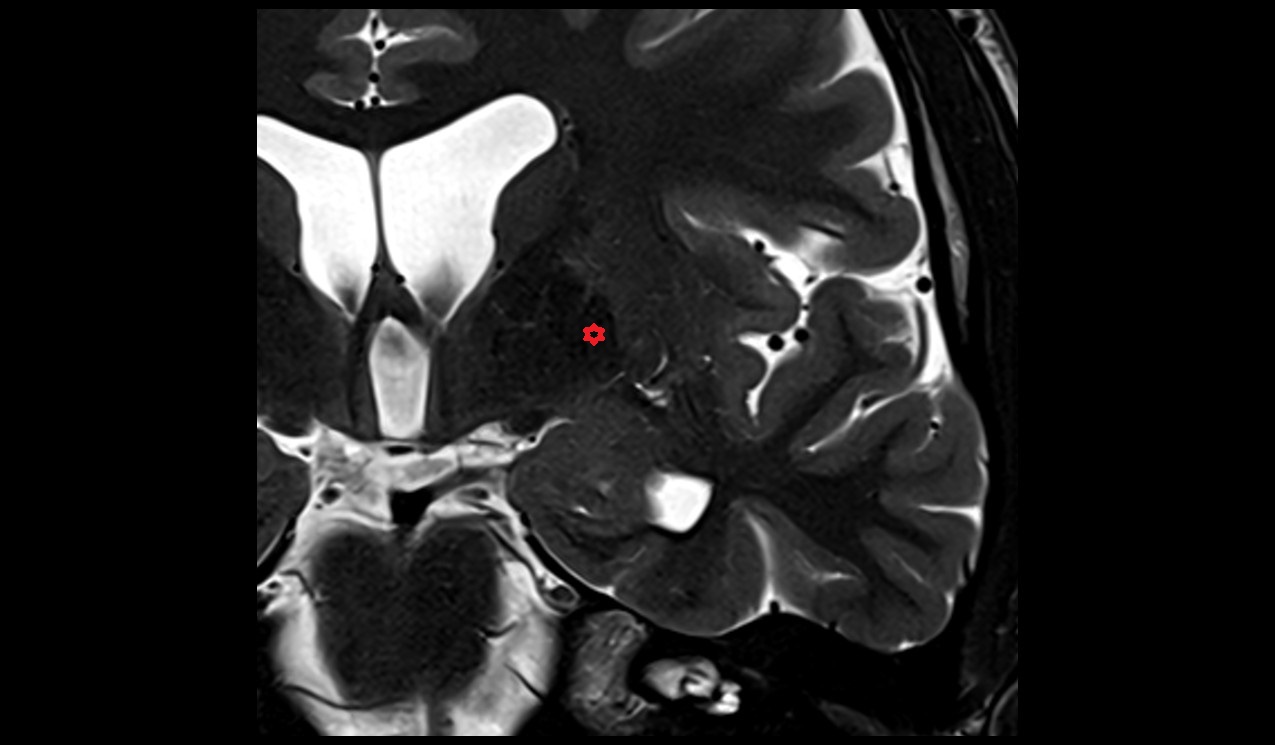

- Hippocampus

- Body of hippocampus

- Head of hippocampus

- Tail of hippocampus